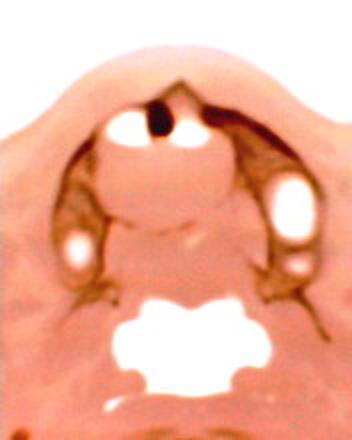

患者:男71岁,右侧上颚肿物无痛性生长7年.

右上颌骨近中线部见类圆形低密度区,上方见一液平,周围见一薄硬化环,前下方见一牙根,后方累及水平板。上方突入鼻腔前下部,下方突入口腔。

考虑:右侧上颌骨囊肿伴感染。